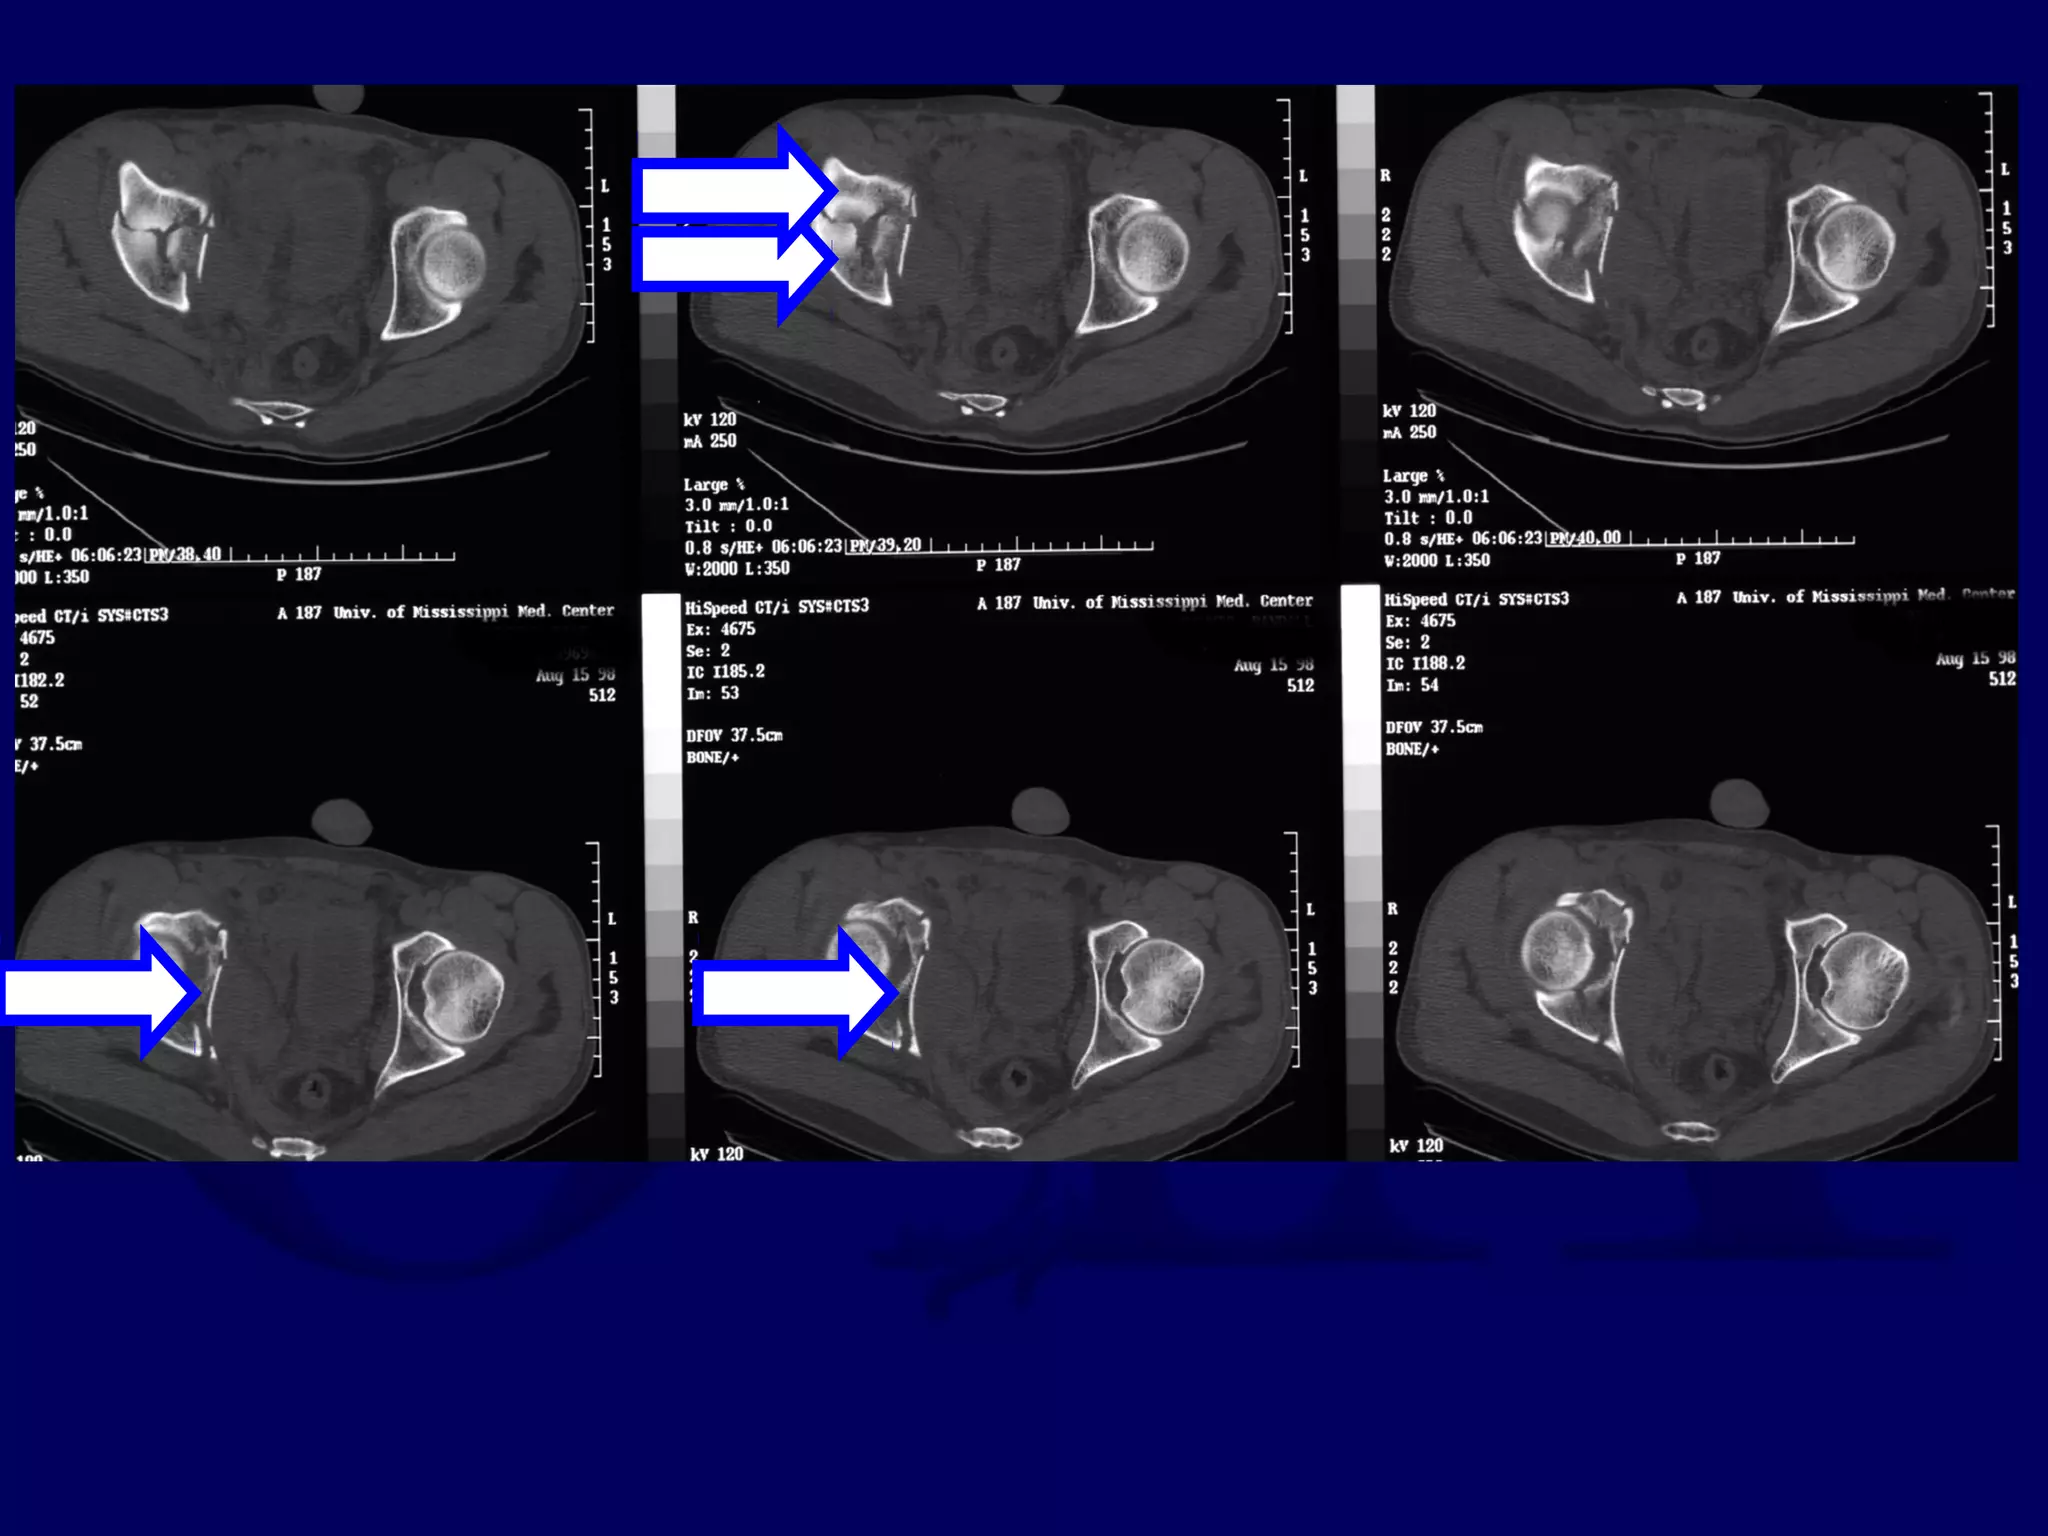

R.M. 98.08.15